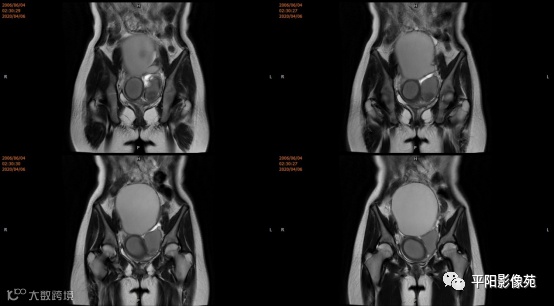

主诉: 下腹部胀痛2+月,加重1天

现病史: 患者月经未来潮,2+月前无明显诱因感下腹部憋胀,间断胀痛,可忍耐,伴排便困难,自认为便秘引起腹胀,未在意。近1+月腹胀、胀痛次数增加,觉下腹部逐渐增大,小便正常。

您的诊断?

宫颈缺如、阴道闭锁

3.CT检查 对子宫、阴道的界限区分有一定限制,对子宫内膜、肌层难以分辨,故CT对子宫先天性异常的研究较少。阴道闭锁时,若宫腔内经血潴留,可见液性低密度聚集,子宫肌层密度均匀。

4.MRI检查 对软组织分辨率好,能够清晰区分子宫及阴道,对子宫内膜、结合带、肌层可清晰分辨;能明确子宫、宫颈、阴道结构异常的部位、范围、性质等。宫腔内经血潴留时,宫腔内见短T1长T2信号。